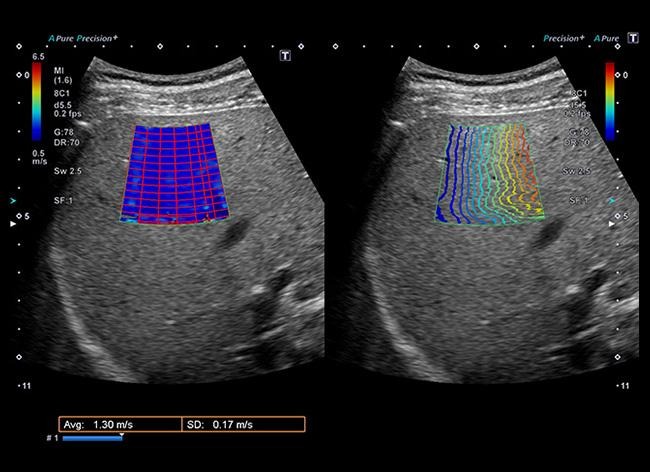

肝疾患の最新検査(ATI・SWE)のご案内

当院では脂肪肝や肝硬変の進行度を客観的な数値で評価できる、最新の超音波解析技術を導入しています。

②SWE(肝臓の硬さを測る)

※SWE(Shear Wave Elastography)は肝臓の「硬さ」を測定する指標です。

脂肪肝や肝炎が放置されると肝臓は徐々に硬くなり(線維化)、肝硬変へと進行しさらに悪くなると癌が出現したりします。SWEは超音波の力で肝臓の硬さ(弾力性)を数値化します。

・メリット:以前は肝臓に針を刺して組織をとる検査(肝生検)が必要でしたがSWEならお腹に装置(プローブ)を当てるだけで、痛み無く安全に硬さを調べることが出来ます。

・こんな方に:慢性肝炎(B型・C型)の方、飲酒量が多い方、脂肪肝が長引いている方。